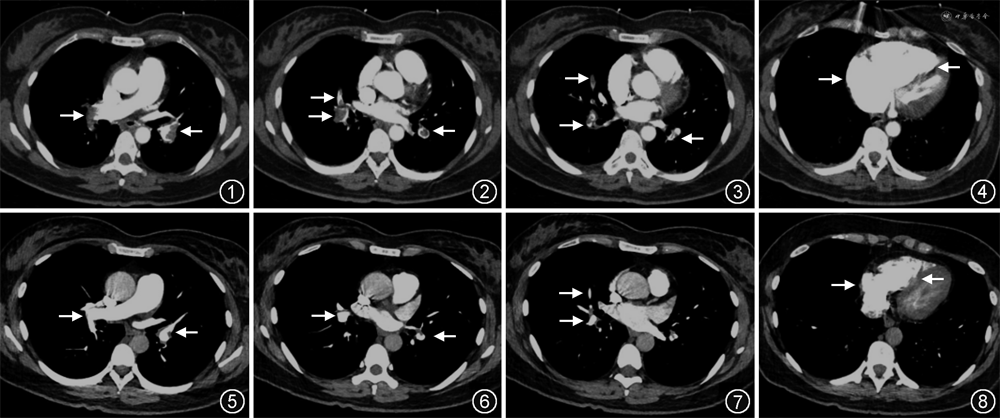

患者女,35岁,因“呼吸困难1个月,下肢肿痛2 d,突发晕厥1 d”于2019年1月12日急诊入院。1个月前患者爬3层楼后出现呼吸困难,症状进行性加重,2 d前突然出现左下肢肿痛,1 d前如厕时突发晕厥,伴抽搐,5 min后自行缓解。发病以来无发热、咳嗽、咳痰、胸痛、咯血、皮疹及光过敏症状。入院时外周指端氧饱和度84%,血压 60/30 mmHg(1 mmHg=0.133 kPa),持续>30 min,呼吸频率26次/min。体检:意识清楚,无颈静脉怒张,双肺未闻及干湿啰音,心率106次/min,律齐,P2>A2,腹软,无压痛及反跳痛,左侧下肢可凹性水肿,双下肢周径:髌骨上缘左侧为57.0 cm,右侧为53.5 cm,髌骨下缘左侧为38.5 cm,右侧为35.5 cm。相关实验室检查:脑钠肽为127 ng/L(0~100 ng/L),肌钙蛋白I为2.33 μg/L(<0.05 μg/L),D-二聚体>35.20 mg/L,血小板为22×109/L,血红蛋白为135.0 g/L,活化部分凝血活酶时间(APTT)为54.1 s,纤维蛋白原(Fbg)为270 mg/L(2 000~4 000 mg/L),生物化学检查:肌酐为85.1 μmol/L,白蛋白为36.4 g/L,谷草转氨酶为123 U/L,谷丙转氨酶为62 U/L,乳酸脱氢酶为544 U/L,α-羟丁酸脱氢酶为348 U/L,碱性磷酸酶为33 U/L,γ-谷氨酰转肽酶为112 U/L,总胆红素为2.9 μmol/L,间接胆红素为1.7 μmol/L。经右股动脉穿刺行血气分析:pH值为7.38,二氧化碳分压为26.3 mmHg,氧分压为53.3 mmHg(吸入氧流量2 L/min)。心脏超声:右心室基底内径40 mm,右心室前壁运动幅度减低,TI法估测肺动脉收缩压(sPAP)54.1 mmHg;下肢静脉超声:左侧股总静脉远端及股浅静脉近端血栓形成。急诊立即给予间羟胺50 mg(5 mg·h-1·kg⁻¹)静脉泵入,维持血压>90/60 mmHg。行肺动脉CT三维成像(CTPA)检查,结果示双肺动脉及分支多发充盈缺损(图1~3),右心明显增大(图4),诊断“高危急性肺栓塞,下肢深静脉血栓形成,血小板减少”。该患者既往无静脉栓塞疾病及出血性疾病病史,无自身免疫疾病,2018年1月患者行子宫肌瘤切除术,术后每月口服屈螺酮炔雌醇片,2个月前停药。

由于患者血压进行性下降,氧合难以维持,权衡利弊,获得家属同意,给予重组人组织型纤溶酶原激活物(rt-PA)50 mg持续静脉滴注2 h进行溶栓治疗。溶栓治疗前采用持续性外周静脉血压监测,一旦血压恢复或发生出血则停用溶栓药物,同时积极与血库联系准备血小板输注。在静脉滴注溶栓药物1 h(rt-PA使用量约25 mg)后,患者咯血约30 ml,呕血50 ml,右侧腹股沟动脉穿刺处出现5 cm×7 cm瘀斑,立即停用rt-PA,急查纤维蛋白原100 mg/L,血红蛋白 95.00 g/L,血小板 57×109/L,立即补充新鲜冰冻血浆200 ml、纤维蛋白原2 g,同时静脉滴注垂体后叶素,奥美拉唑泵入抑酸,腹股沟局部加压止血。监测血压为101/59 mmHg,停用血管活性药物,严密监测病情,患者未再发生咯血及呕血,腹股沟处瘀斑未进一步扩大。溶栓结束后2 h测血压 103/67 mmHg,复查血红蛋白 97.00 g/L,血小板 78×109/L,纤维蛋白原770 mg/L。4 h后测APTT 61.3 s,8 h后测APTT 42.7 s,开始普通肝素泵入抗凝治疗,将APTT维持在40~50 s。入院后行常规肿瘤标记物检查未见异常;生物化学检查抗核抗体、抗dsDNA、自身抗体、风湿因子、类风湿因子、抗中性粒细胞胞质抗体(ANCA)、心磷脂抗体、狼疮抗凝物、抗β2-糖蛋白1抗体、抗环胍氨酸肽抗体和抗肾小球基底膜抗体均未见异常;同型半胱氨酸和易栓症排查未发现异常。2周后复查CTPA见双肺动脉充盈缺损较前减少(图5~7),心脏超声回报右心功能正常,右心室基底内径33 mm(图8),于2019年2月1日出院,出院后3个月及1年随访均未见血小板减低。